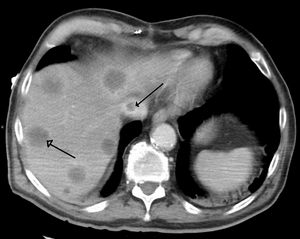

| Budd–Chiari syndrome secondary to cancer; note clot in the inferior vena cava and the metastasis in the liver | |